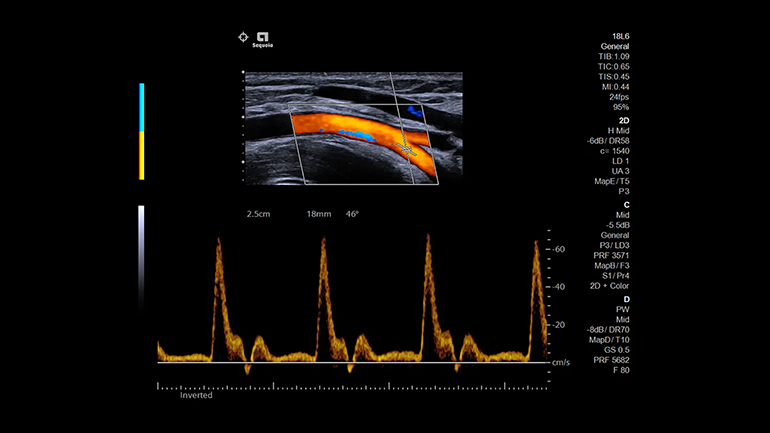

Система Acuson Sequoia учитывает биоакустические вариации каждого пациента – это характеристики, включающие плотность ткани, и способность к поглощению и рассеянию сигнала. Система обеспечивает визуализацию тканей с высоким разрешением во всем поле зрения. Таким образом, специалисту не требуется корректировать зону фокуса сканера, а это ускоряет исследование без потери качества. Кроме того, новая система обеспечивает цветное допплеровское картирование кровотока с высоким разрешением, чувствительностью и глубиной проникновения (в среднем на 20% выше, чем у других систем).

Технологии цветовой визуализации

Технология улучшенного отображения просвета сосудов Clarify Vascular Enhancement

Технология Clarify Vascular Enhancement позволяет уменьшить количество артефактов, часто встречающихся на изображениях просвета сосудов и камер сердца плода, улучшает дифференцировку границ сосудов, позволяет значительно повысить качество визуализации сосудов малого диаметра.

Технология Slow Flow State

В технологии Slow Flow используются интеллектуальные фильтры, которые позволяют выделить кровеносные сосуды с помощью фильтрации движения, адаптивно улучшают ЭХО- сигнал и подавляют артефакты яркости. Эти интеллектуальные фильтры могут обнаруживать и маркировать низкоскоростной кровоток, который в противном случае был бы смешан с шумовыми артефактами и исключен из визуализации из-за скоростных ограничений, применяемых в обычном допплеровском режиме.

Технология Dynamic MultiHertz

Интеллектуальный инструмент автоматизации исследования, который автоматически регулирует частоту сканирования в В-режиме и в цветовом режиме в соответствии с положением окна цветового изображения.

Технология Auto TEQ Doppler УЗ-сканер экспертного класса ACUSON Sequoia может автоматически регулировать кривую импульсно-волнового допплеровского режима на стоп-кадре, чтобы обеспечить уверенность в рабочем процессе. Для улучшения рабочего процесса пользователь также может воспользоваться всеми возможностями постобработки.